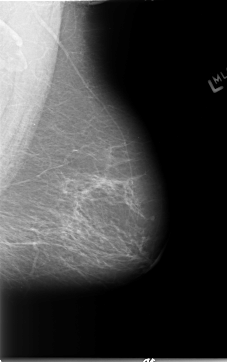

B_3090_1.RIGHT_MLO

LEFT_MLO LINES 5792 PIXELS_PER_LINE 3632 BITS_PER_PIXEL 12 RESOLUTION 50 NON_OVERLAY